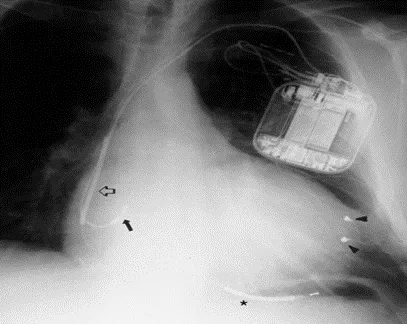

心脏的再同步化治疗(CRT)--双心室起搏、三腔起搏

3. CRT-P治疗是点睛之笔,心房电极增加了基于AV波的鉴别功能,双室起搏基于III°房室阻滞而免于房室结消融,较窄的QRS波消除了室内不同步,后期的心脏充分正重构避免了除颤线圈对右室的不利影响;